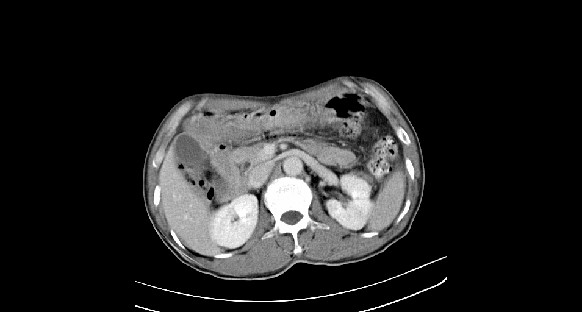

男性,70岁,体检b超发现左肾占位,请各位战友发表一下观点

左肾有两个病灶,且较大的病灶内可见点状钙化灶,增强扫描边缘也是呈渐进性强化,中央部分未见明显强化